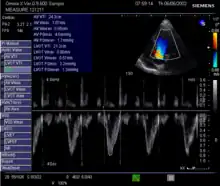

Echocardiography

Echocardiography is a non-invasive method of quantifying cardiac output using ultrasound. Two-dimensional (2D) ultrasound and Doppler measurements are used together to calculate cardiac output. 2D measurement of the diameter (d) of the aortic annulus allows calculation of the flow cross-sectional area (CSA), which is then multiplied by the VTI of the Doppler flow profile across the aortic valve to determine the flow volume per beat (stroke volume, SV). The result is then multiplied by the heart rate (HR) to obtain cardiac output. Although used in clinical medicine, it has a wide test-retest variability.[8] It is said to require extensive training and skill, but the exact steps needed to achieve clinically adequate precision have never been disclosed. 2D measurement of the aortic valve diameter is one source of noise; others are beat-to-beat variation in stroke volume and subtle differences in probe position. An alternative that is not necessarily more reproducible is the measurement of the pulmonary valve to calculate right-sided CO. Although it is in wide general use, the technique is time-consuming and is limited by the reproducibility of its component elements. In the manner used in clinical practice, precision of SV and CO is of the order of ±20%.